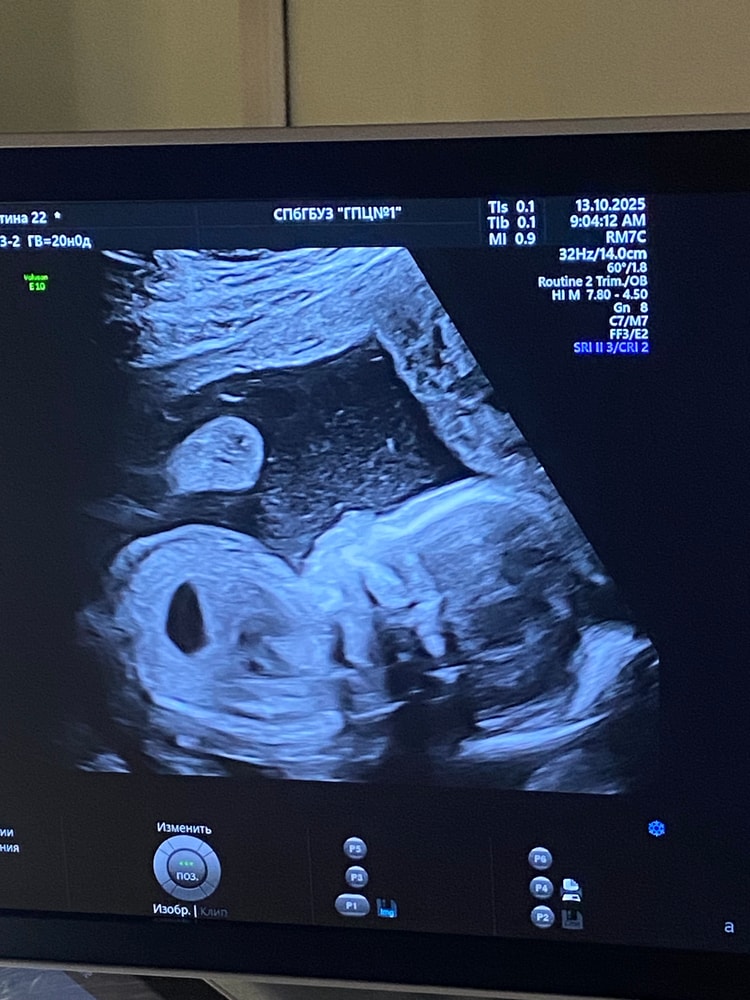

Анализы, скринингиСкрининг прошла, все хорошо! Малышка развивается замечательно.

знающие люди, подскажите, а что это за черное пятнышко на узи? Это ребенок поел перед узи, это желудок?😁